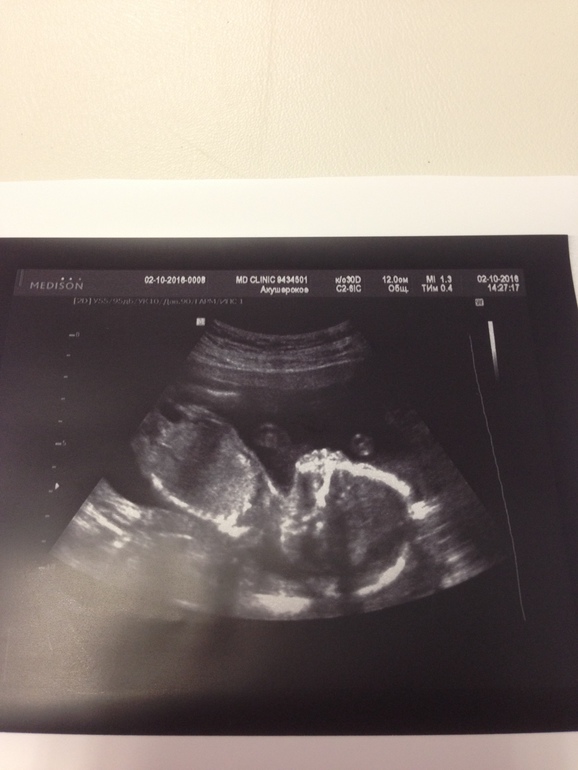

Сегодня сходила на узи был скрининг ну и конечно же посмотреть как малышка при моей болезни.

Доченька растёт тттт, но все так же идёт с отставанием из-за поздней овули.

Сегодня у нас по месячным 19.2, а Василиска на 18.5, не страшное отставание😍😍😍

Вес сегодня 261 грамм счастья💞💞💞

Лежит оченььь низко и это не айс, буду носить бандаж что бы держать её повыше, видимо мышцы не держат уже столько беременностей.

Плацента моя нифига не поднимается как была у края так торчит там.

Шейка тттттт 40, в прошлую беременность были проблемы.

Ну и моя малышка тттттт